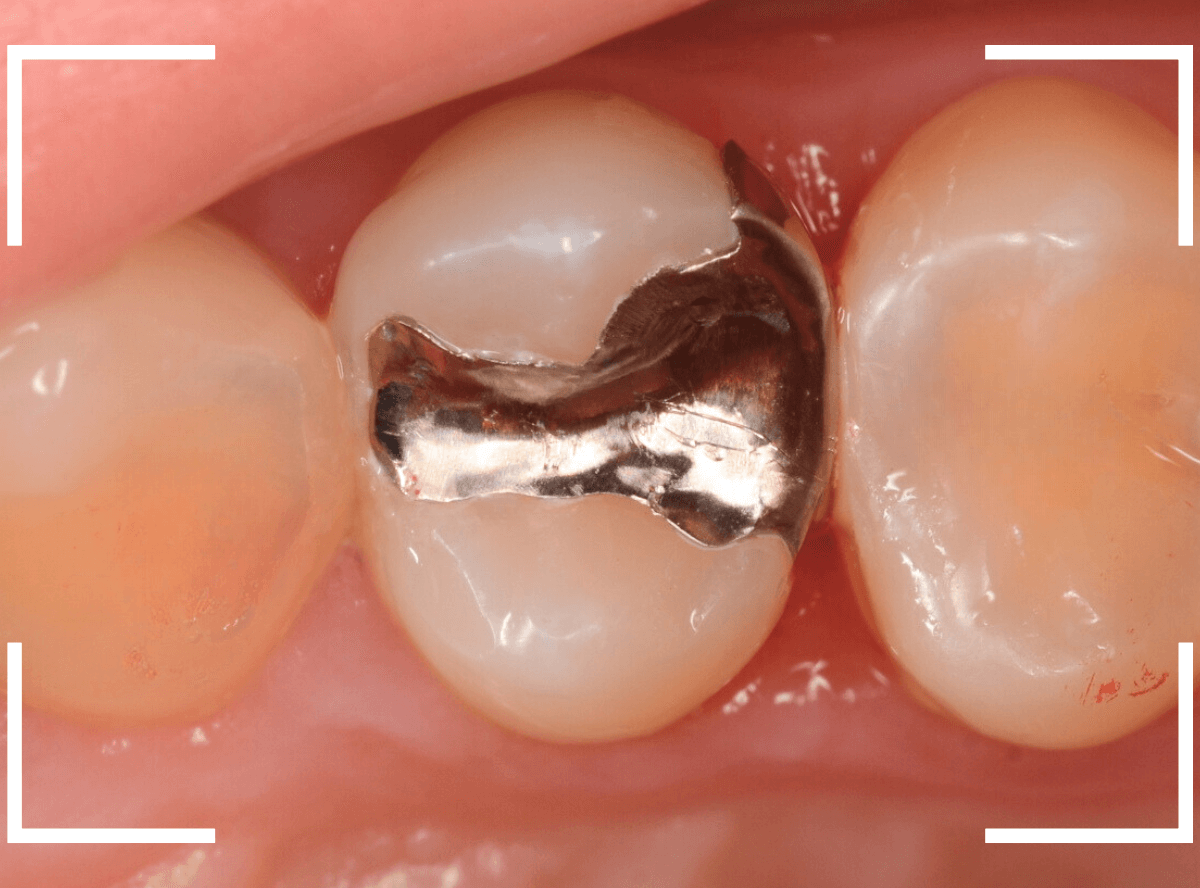

Case.25 レントゲン所見と目視を頼りに、虫歯治療

検査時に〇部、歯と歯の間の小臼歯部に虫歯らしき黒い影があるのが見つかりました。

かなり怪しいですが、メタル・インレーが入ってるので、それが透けている可能性もあります。

レントゲン写真で確認します。

レントゲンでは後ろの大臼歯部の方が虫歯になっているように見え、小臼歯部は問題ないように見えます。

まず大臼歯のインレーを外して、中を調べます。

あれ、インレー直下は虫歯がなさそうです。

レントゲン写真を頼りに、歯を削ると、虫歯が出てきました。

大臼歯の虫歯を削っていくと、手前の小臼歯まで虫歯がつながっていました。

やはり、黒い影は虫歯でした。これは深そうです。

メタル・インレーも外して、虫歯を除去します。

全ての虫歯を除去しました。

レントゲン写真では確認できませんでしたが、手前の小臼歯は深い虫歯でした。

このように、歯と歯の間の虫歯は、深い事が多いです。